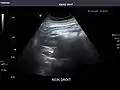

Liver